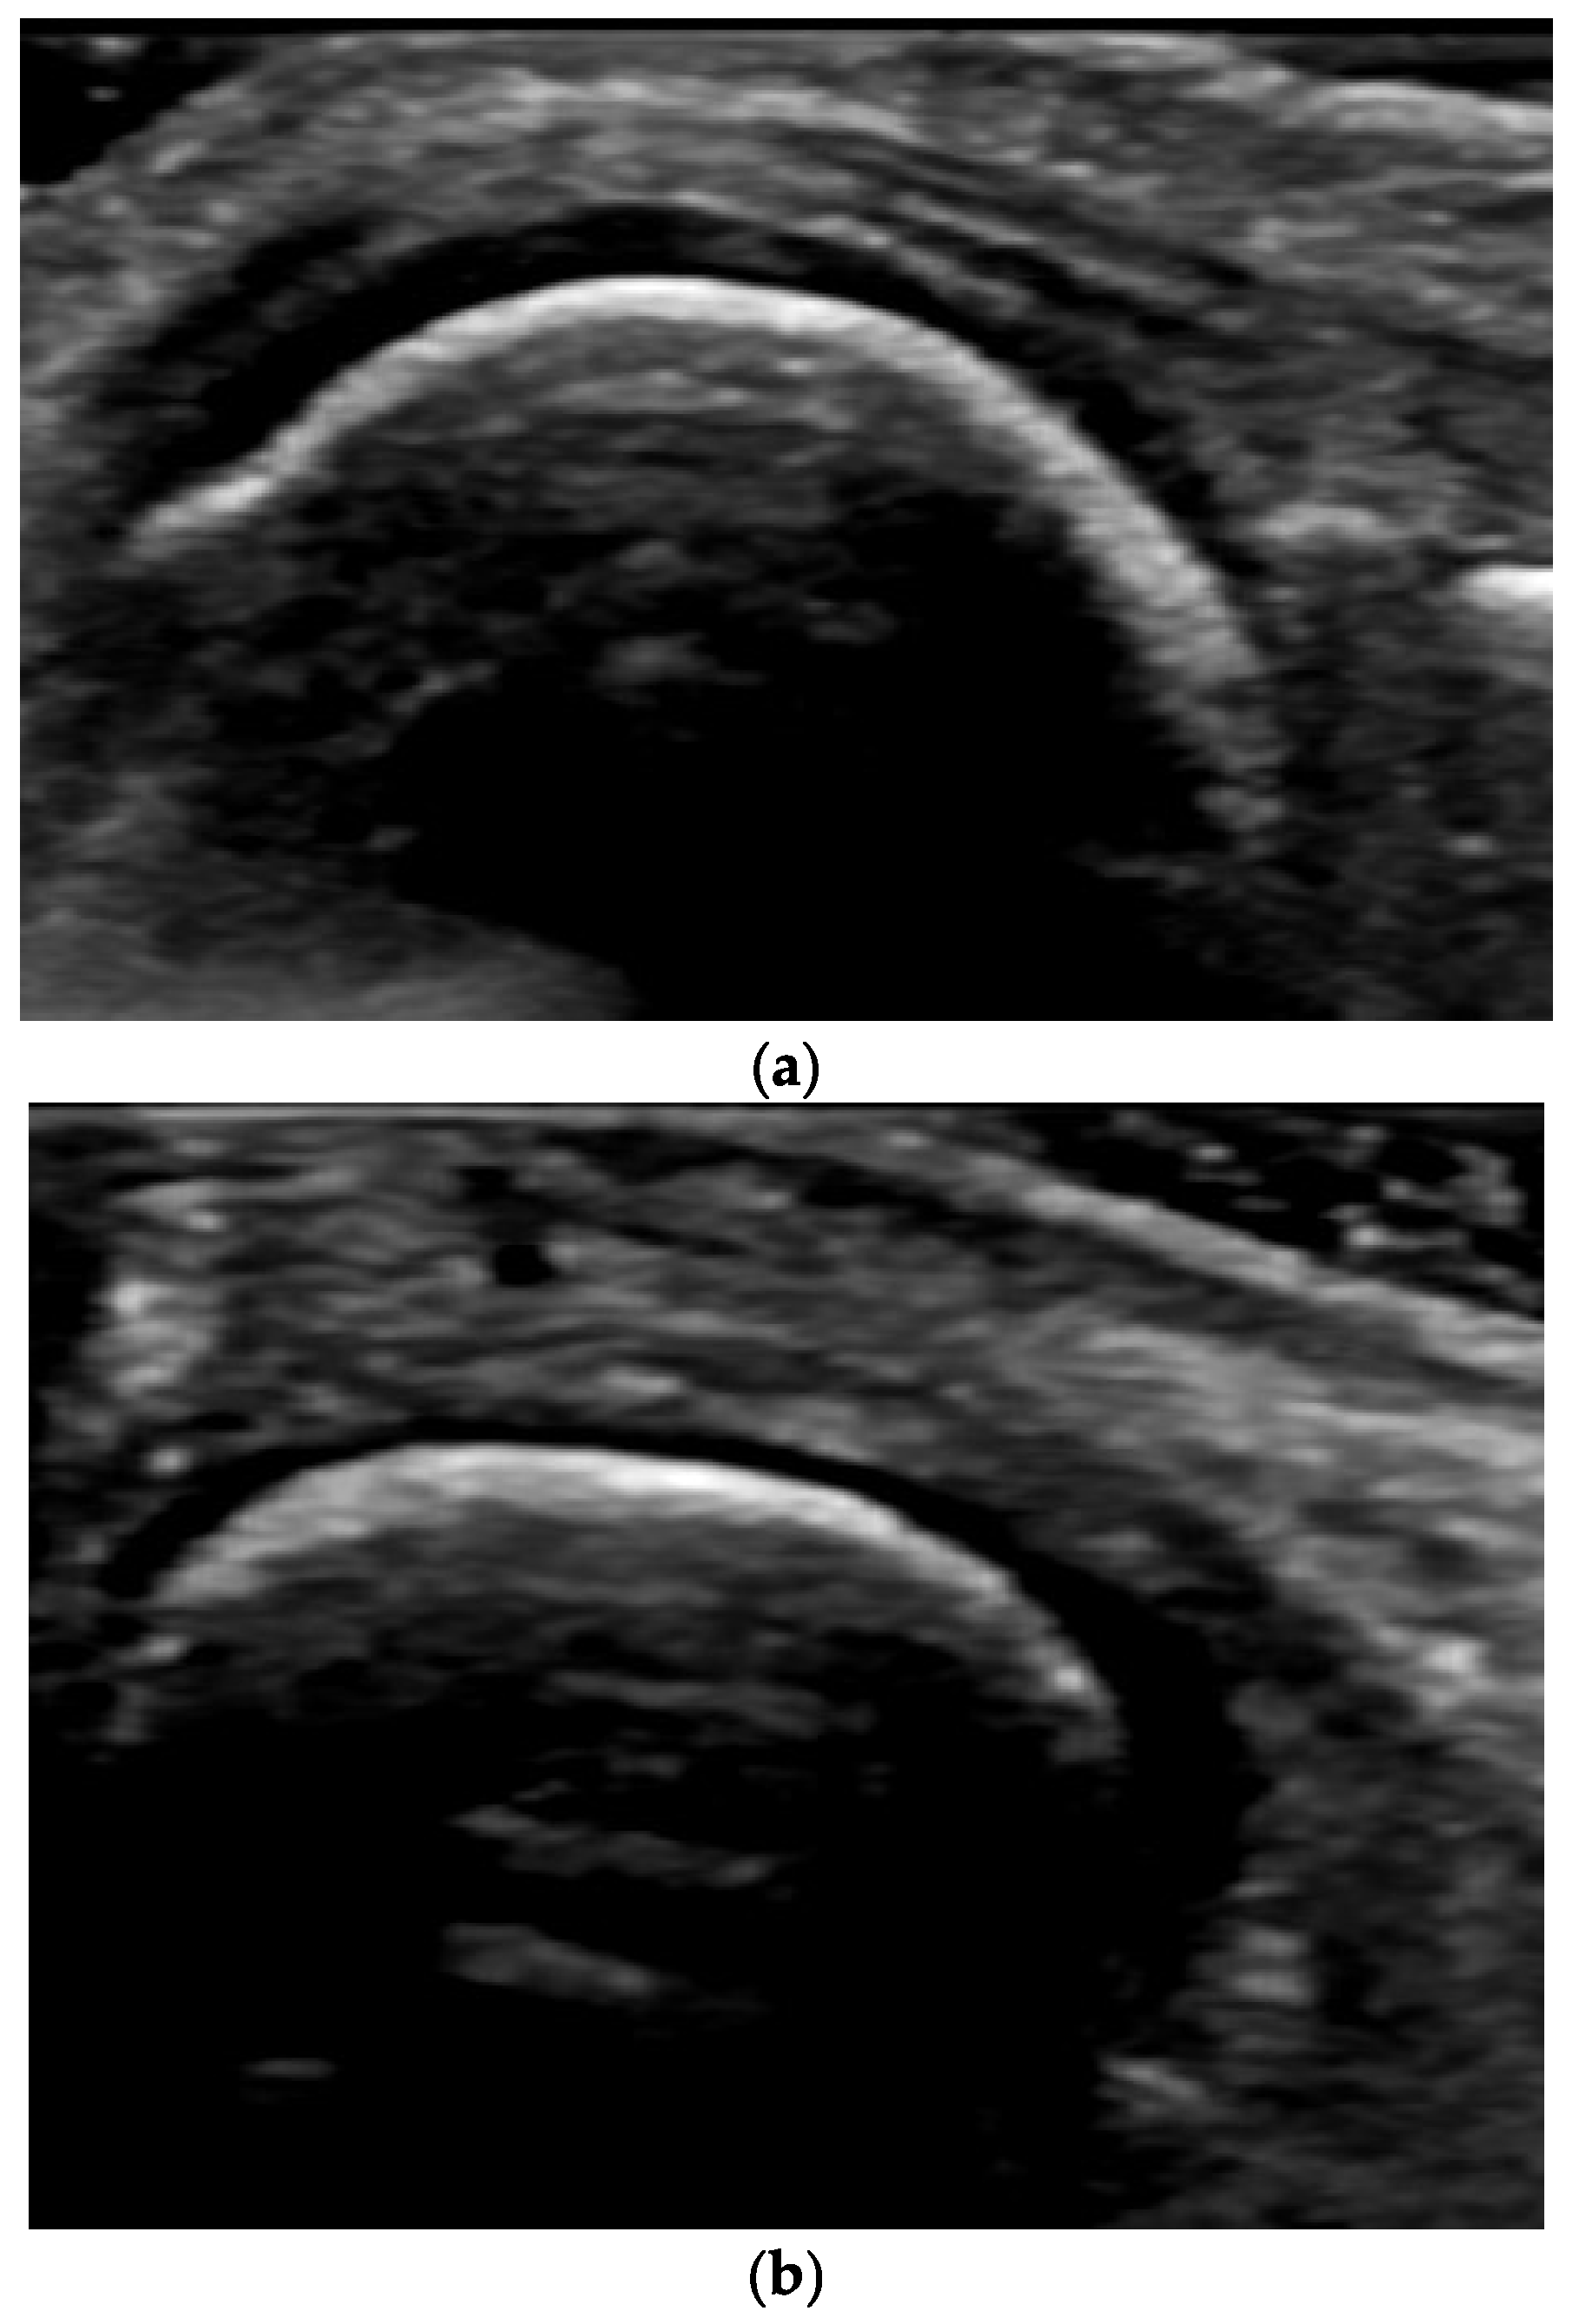

4. Examples of US Phenotypes